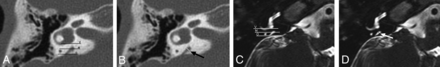

The third group had a diagnosis of EVA on HRCT with a diagnostic MR imaging available for review. This group included 24 patients and 48 ears, with an age range from 0.5 to 15 years (mean, 6.6 years; M/F ratio = 1:1.4). Three patients had a diagnosis of Coloboma of the eye, Heart defects, Atresia of the choanae, Retardation of growth and/or development, Genital and/or urinary abnormalities, and Ear abnormalities and deafness (CHARGE) syndrome. Bilateral EVA was present in 14 patients, and unilateral, in 10, with 38 ears having an EVA on CT (Fig 5). The mean VA size was 1.7 mm, and the median VA size was 1.6, with a range of 0–4 mm. By means of a cutoff of 1-mm midaperture width, only 1 ear was misdiagnosed as normal on MR imaging, with the ELD measuring 0.9 mm on MR imaging compared with the VA measuring 1.6 mm on HRCT (Fig 6). All normal VAs on CT were measured as normal ELDs on MR imaging. With HRCT as the standard, sensitivity for demonstrating an enlarged ELD using MR imaging was 97% (95% CI, 86%–100%) with a specificity of 100% (95% CI, 69%–100%) for the first reader. For the second reader, sensitivity was 89% (95% CI, 75%–97%) and specificity was 90% (95% CI, 56%–100%). Intraclass correlation coefficients calculated for interrater agreement were 0.89 (95% CI, 0.81–0.93) on MR imaging and 0.91 (95% CI, 0.84–0.95) on CT.

Axial HRCT (A and B) shows the vestibular (V) and opercular (O) planes used to define the VA midpoint (M), and an EVA measuring 1.6 mm (arrow). MR imaging (C and D) in the same patient shows the corresponding vestibular (V), opercular (O), and midpoint (M) planes and a normal-sized ELD measuring 0.9 mm (arrow).